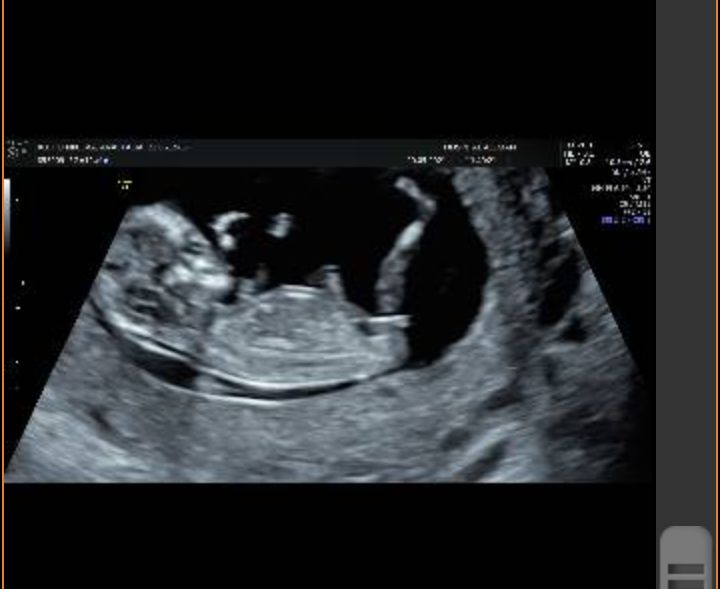

Девочки,может кто-то разбирается))возможно ли понять по узи пол малыша?)на 1 скрининге не сказали.

По бугорку девочка)

Но у нас тоже по бугорку в 11 нед девочка.

А на скрининге в 13 нед говорят мальчик.

Ждём дальше)

Девочка ,точно такой бугорок у нас и в 20 недель подтвердили что девочка

Ольга, это мы на 11+6 недели и точно как у вас ,девочка 🙈